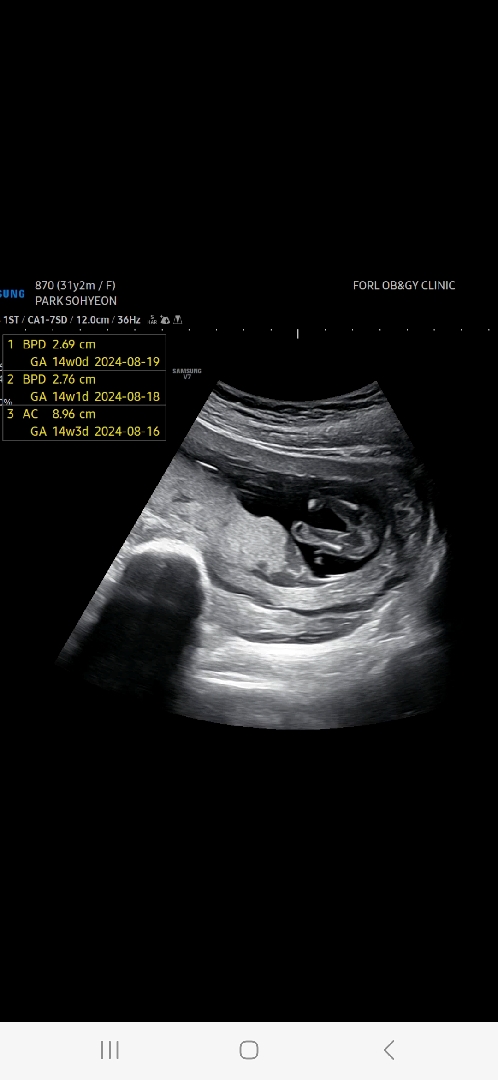

오늘 너무 궁금해서 서브병원 다녀온 14주차3일 초음파에용 의사쌤께서 "엄마 닮을 확률이 크네요 ^^ 다리사이가 밋밋하네요 조금 더 지켜보죠 ㅎㅎ " 라고 하셨는데 딸일까요 ?! 초음파 고수님들 봐주세용 ㅜㅜ

오! 딸 맞는것 같아요!! 제 게시물 보시면 비교가 될거에요!